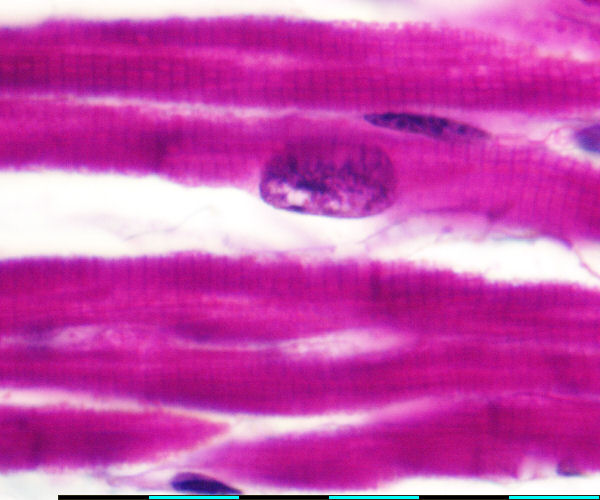

back heart muscle fiber